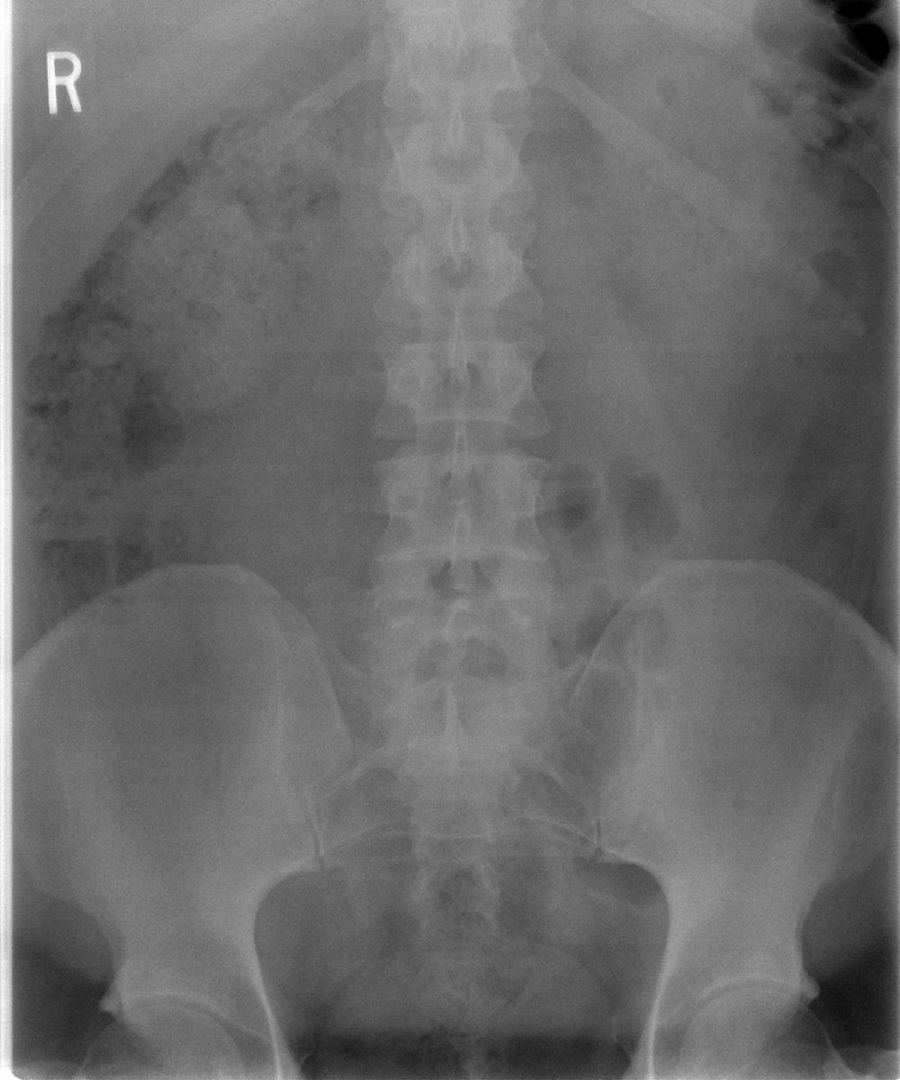

Como tratar con la espondilodiscitis infecciosa

La espondilodiscitis infecciosa es una infección poco frecuente que afecta a las vértebras y al espacio intervertebral. Generalmente son bacterias las que lo producen y que suelen llegar a la columna a través del torrente sanguíneo o directamente tras una operación en la zona.

Las vértebras a las que principalmente suelen afectar son las lumbares, seguido de las dorsales,  siendo las cervicales las menos frecuentes. Esta infección suele ser complicada de diagnosticar puesto que se manifiesta con un dolor de la zona de la espalda donde están las vértebras afectadas y que siempre se suele relacionar primero con contracturas u otros problemas asociados a los dolores de espalda. El dolor suele ir aumentando con el tiempo pudiendo llegar a ser casi incapacitante, sobre todo si la infección se extiende y produce compresión medular.

A pesar de tratarse de una infección, sin embargo, no siempre provoca fiebre y eso retrasa su diagnóstico, unido a que no siempre se puede detectar con un simple análisis de sangre como otros procesos infecciosos. Generalmente se necesita una resonancia magnética para localizarla y en algunos casos se requiere de una biopsia para determinar cuál es la bacteria que ha producido la infección.

El tratamiento consiste en el suministro de antibióticos específicos para acabar con la bacteria durante varias semanas y en algunos casos es necesaria la intervención quirúrgica para dejar 'limpia' la zona con el fin de garantizar la oxigenación de los tejidos de las vértebras afectadas y garantizar la movilidad y seguridad de la columna vertebral.